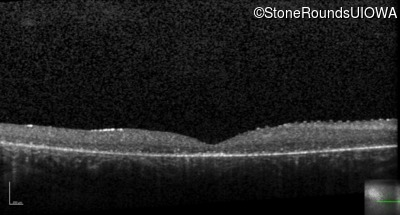

Optical Coherence Tomography - Right - 20/200 sc

Exemplar / OCT Stack